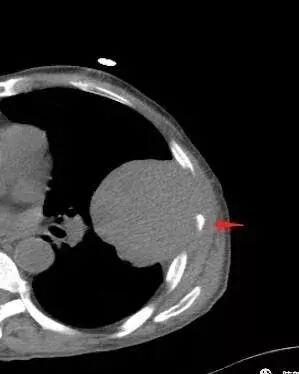

胸壁来源符合吗?

不符合,因为病灶的主体在肺内,而且胸膜在病灶的外侧为主

与胸膜非钝角相交

病灶的整体形态--肺内边界清晰,膨胀性为主

如果是外面长进来的,胸膜掀起的角度一般更大,呈钝角

我们换个角度讲,如果是胸壁肋骨来源,病灶外朝内生长,并且朝内生长这么大,按理说应该是内侧侵袭性强,外侧侵袭弱。但是看这个病灶,外侧边界反而不清,内侧边界清,整个形态不太符合肋骨来源,而且胸膜局部增厚也不太符合胸壁来源。我认为肋骨来源应该以肋骨为中心,偏侧可以,但不会这么明显。而且血供也不一致,应该是肋间或胸壁动脉明显。

肋骨内侧面破坏为主,朝外有轻微的推移迹象。我觉得胸壁来源的放后面,特别是支气管的堵塞,这是肺外病变很少见的,SFT也有,罕见。